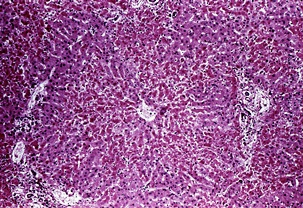

황달이 생기는 이유는 담즙색소라고 알려진 빌리루빈이 과도하게 생기기 때문입니다. 빌리루빈은 우리 몸의 오래된 적혈구가 파괴되면서 생기는 물질인데요. 이 물질은 담즙에 녹아서 우리 몸의 배설물과 함께 배출이 되는 것이 정상적이지만 빌리루빈의 과잉생산이나, 간의 장애, 간세포나 담도의 손상에 의해 빌리루빈이 역류할 경우 발생된다고 합니다.

황달이 생겼을 때 나타나는 대표적인 증상은 소변의 색깔이 진하게 변하는 것입니다. 이는 과도하게 분비된 빌리루빈이 소변으로 배출되기 때문인데요. 이러한 경우 소변의 색이 진한 갈색으로 변하게 됩니다. 또한 피부에 담즙색소가 침착되면 눈이 노랗게 변하는데요. 눈에 노랗게 된다고 모두 황달 증상을 의심할 수 있는 것은 아닙니다.

보통 눈과 피부, 소변의 색깔에 모두 이상이 생긴 경우 황달 증상으로 볼 수 있으며 병원에 내원하여 진단을 받아보는 것이 권장됩니다. 황달이 생기는 경우 피부 가려움증을 동반한다고 하는데요. 이러한 이유는 배출되어야 할 화학물질이 피부의 신경조직을 자극하여 발생한다고 추측하고 있습니다.